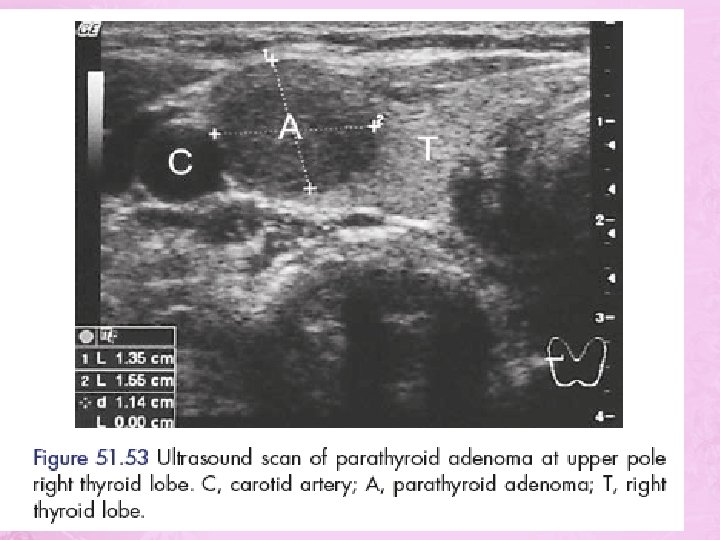

Hyperparathyroidism • Symptoms of over activity of the para thyroid gland may result from single or multiple adenoma (85%) • Hyperplasia of all 4 glands 13% • Carcinoma more than 1%. • That whole glands enlarged, darker in color. Firmer and more vascular.